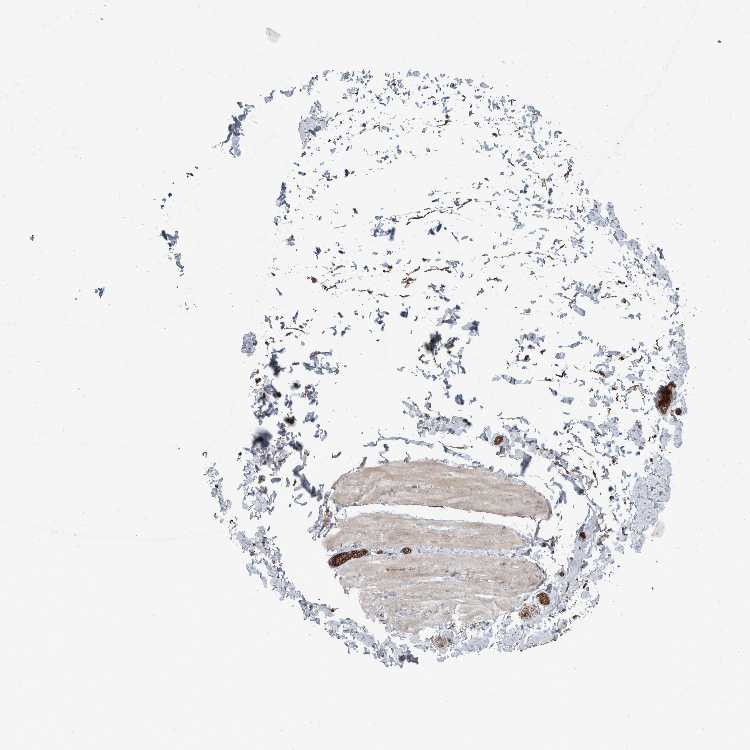

SOFT TISSUE 2 - Antibody stainingi

Antibody staining in the annotated cell types in the current human tissue is reported as not detected, low, medium, or high, based on conventional immunohistochemistry profiling in selected tissues. This score is based on the combination of the staining intensity and fraction of stained cells.

Each image is clickable and will lead to virtual microscopy that enables deeper exploration of all samples and also displays staining intensity scores, fraction scores and subcellular localization as well as patient and tissue information for each sample.

Antibody HPA026904

Fibroblasts Medium

Peripheral nerve Not detected